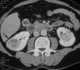

Large kidneys with multifocal masses

May Be Caused by

Acquired renal cystic disease

Angiomyolipoma

Autosomal dominant polycystic kidney disease

Bilateral renal cell carcinoma

Bilateral Wilms tumor

Burkitt lymphoma

Lymphoma

Metastases

Multiple renal cysts

Nephroblastomatosis

Tuberous sclerosis

Von Hippel-Lindau disease